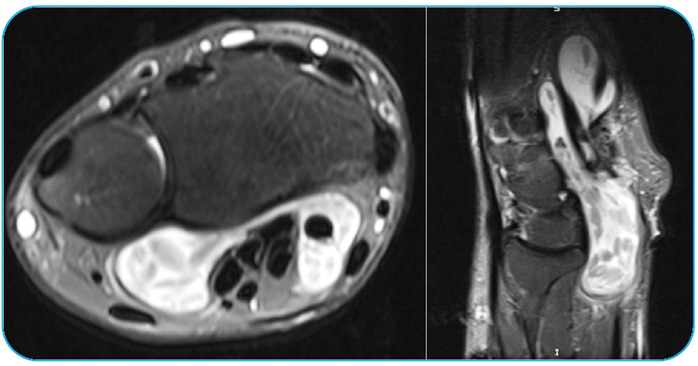

3 Mart 2026Yazar Op. Dr. Vahit Mutlu Tarih 3 Mart 2026Kategori BlogKist Hidatik Nedir? Karaciğerde Sessiz İlerleyen TehlikeKist hidatik, halk arasında “köpek kisti” olarak bilinen ve özellikle karaciğeri tutan bir parazit hastalığıdır. Etkeni, Echinococcus granulosus adlı bir tenyadır. Bu hastalık özellikle: Hayvancılıkla uğraşılan […]